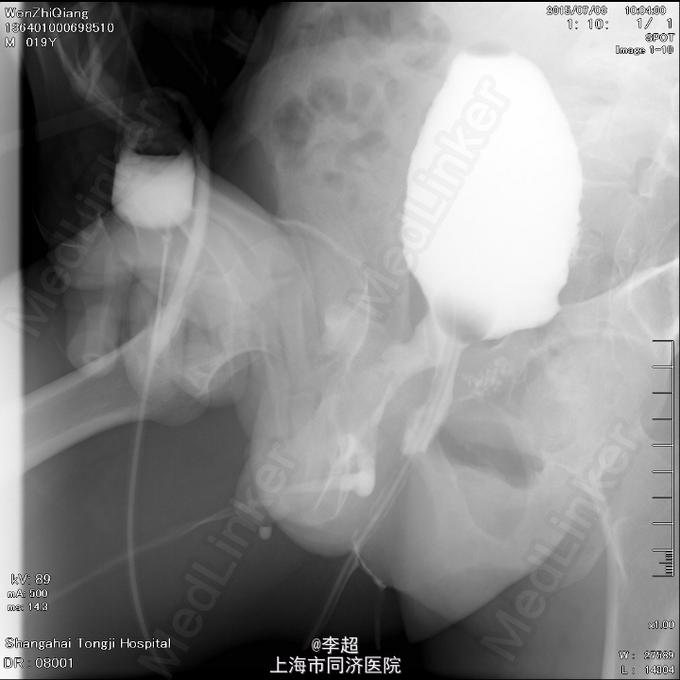

择期行耻骨下缘切除+阴囊皮瓣代尿道成形+尿道膀胱拖入术 手术过程:行会阴部倒Y形切口切口,切口包括会阴部尿道造口处,术中见阴茎部尿道存在尿道-阴茎皮肤瘘道,予切除瘘道。分离后尿道,探查见后尿道疤痕明显,并且于耻骨相连,局部粘连严重。考虑有假道存在可能,遂做耻骨上纵行切口4cm,探查膀胱发现距目前尿道口处1cm处前方存在另一内口,为盲道,盲端被变形耻骨完全遮挡。遂使用骨刀劈凿穿耻骨并切除耻骨下缘,凿通至膀胱盲道,将盲端断断显露,使用膀胱镜探查盲道,见盲端口膀胱肌肉括约功能较好,推断为真性尿道,使用左侧阴囊及大腿根部皮瓣约8cm*3cm大小,分离皮瓣下组织血管形成血管蒂,翻转皮瓣形成尿道,将皮瓣尿道近端拖入膀胱,与真性尿道膀胱黏膜处直针缝合。另将皮瓣尿道远端与阴茎部正常尿道粘膜缝合,留置F14号导尿管,假道处尿道予留置Foley14导尿管。

随访 讨论

术后6周拔除尿管,患者排尿通畅,无尿失禁,尿流率17ml/s, 术后8周拔除假道内导尿管,拔管后2周假道自行闭合。 该患者尿道缺失长,且尿道断裂处被变形耻骨完全遮挡,故外院手术时,从骨头下方吻合,形成假道。 本次手术后,恢复正常的尿道结构,和尿道内口位置,故尿失禁症状消失。 但手术难度极大,缝合时没有操作空间,凿去骨头后,仍仅能行直针拖入缝合。但吻合较确切,故术后效果良好。